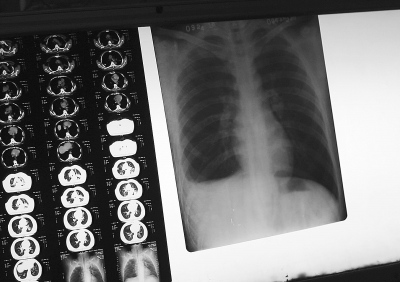

2009年3月24日,河北赵县,结核病人的X光片。